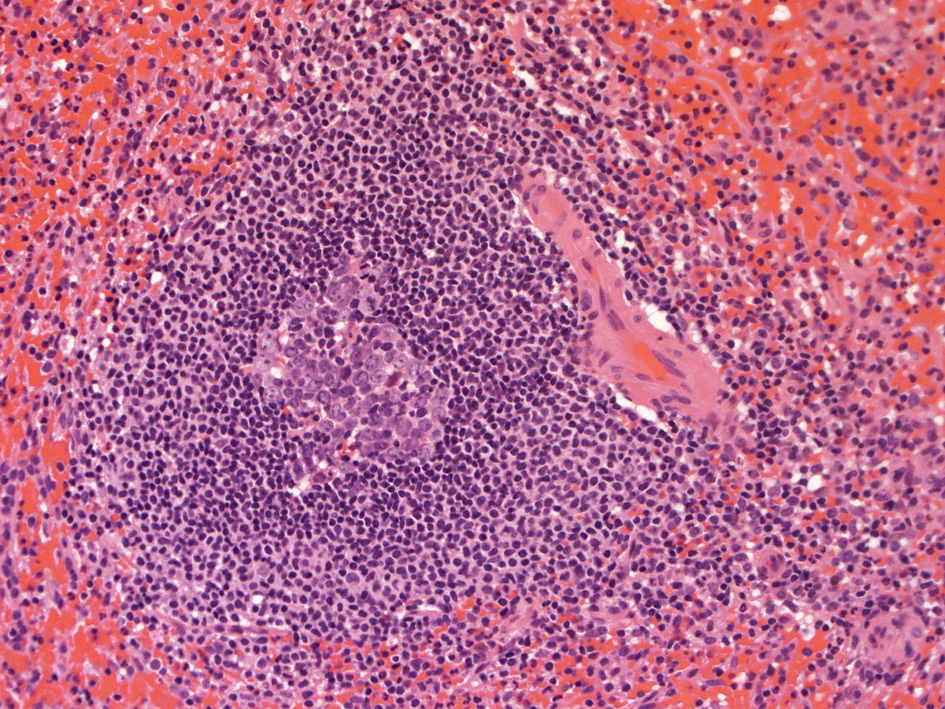

白脾髄の構造

spleenA011.jpg

白脾髄, 辺縁帯/周辺帯は脾臓のリンパ装置として機能する. 開放性末梢血管流床を介して伝達される免疫情報はこれらのリンパ装置で処理され効率よく免疫反応がおこる.

白脾髄 white pulpは中心動脈周囲に形成されているリンパ組織で, 動脈周囲リンパ鞘 periarteriolar lymphoid sheath(PALS)とリンパ濾胞(lymph follicles)の異なる2つの領域が識別される.

脾動脈脾柱という結合組織を通って実質内に入るところから毛細血管に至るところまで、その周囲にリンパ鞘(リンパ鞘=PALS/ peri-arterial lymphatic sheathの略)が形成され、所々にリンパ濾胞が発達している. 濾胞内には胚中心が見られることが多い。胚中心の周りには暗調にそまる小型のリンパ球がマントル層を作って取り囲む。リンパ鞘もリンパ節の構造と同じく粗で不規則な細網線維からできたネットワークが骨格となっている。

リンパ鞘はT細胞領域リンパ濾胞はB細胞由来です。PALSのT-cellsはCD4+ cell > CD8+ T-cells

PALS, 動脈周囲リンパ鞘 periarteriolar lymphoid sheath

リンパ濾胞

辺縁帯/周辺帯 Marginal zone

胚中心が多数出現しているときはなんらかの抗原刺激を受けたと考えられる.

慢性感染症がある人の脾臓や特発性血小板減少性紫斑病の人の脾臓では胚中心が特に発達している. 一方で自己免疫性溶血性貧血では胚中心は少なく、先天性球状赤血球症ではほとんど見られない.